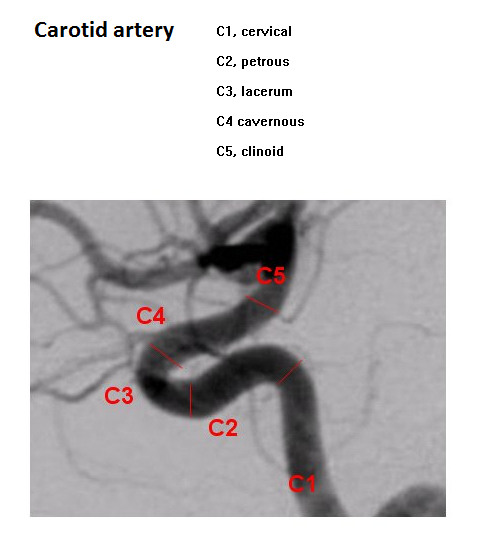

• Anterior circulation Brain